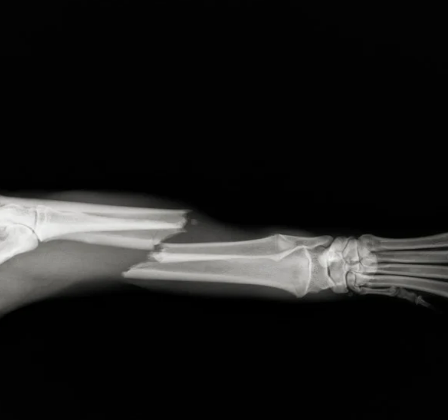

- X-ray(필수), 필요 시 CT/MRI(관절·성장판·척추/신경 평가)

- 수술적 치료: 변형·불안정·분쇄·개방·성장판/관절내 골절 →

- 핀/와이어(수내정)

- 플레이트 & 스크류(미니플레이트 포함)

- 외고정 장치(ESSF) 등

미니플레이트/스크류는 고정력이 뛰어나고 골수강 손상이 적어 치유 속도·정렬 유지에 유리. 다만 크기·각도·뼈 상태에 맞춘 정밀 선택이 필요해요.